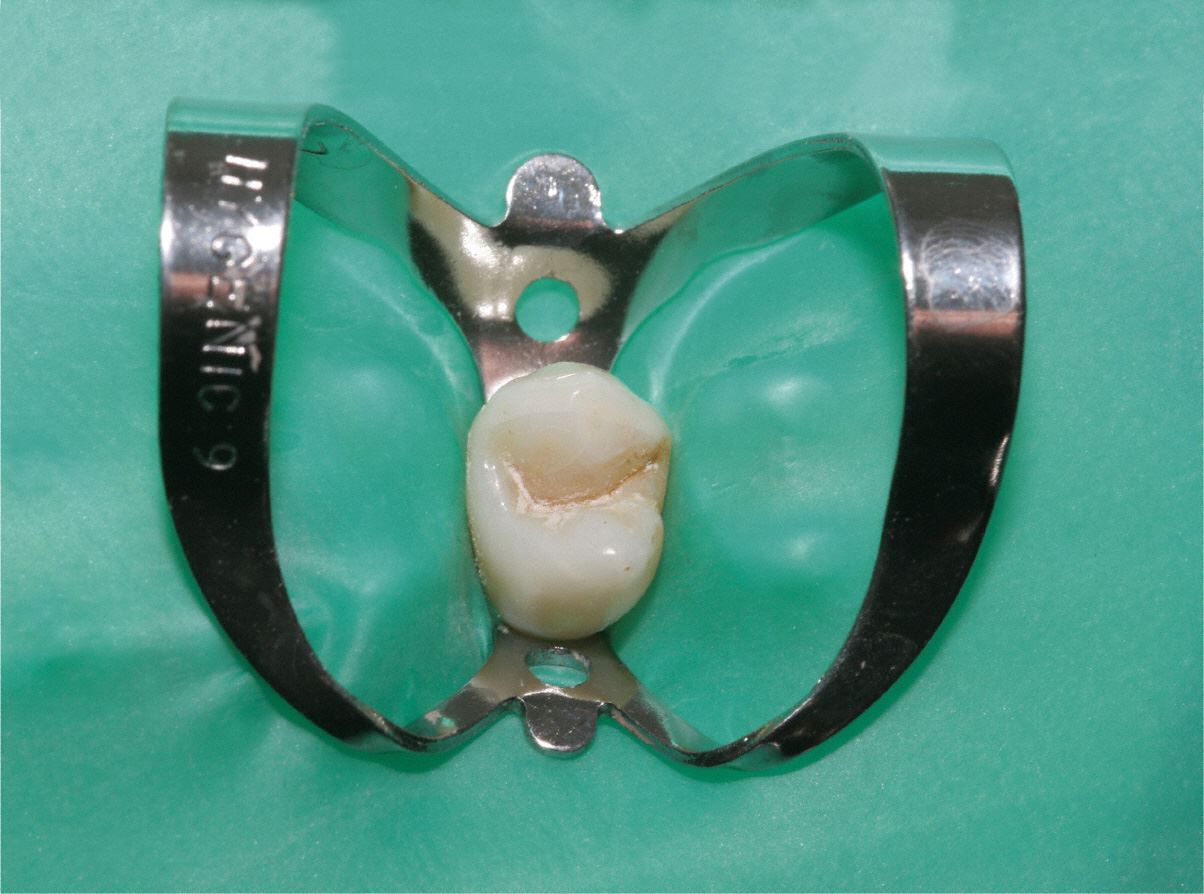

Dafür benutzt man einen speziellen Spanngummi, genannt "Kofferdam", der sowohl den Zahn isoliert, als auch das Eindringen von Bakterien aus der Mundhöhle in den Zahn verhindert. Gleichzeitig wird vermieden, dass der Patient kleine Instrumente oder Materialien verschluckt. Bild: Kofferdam